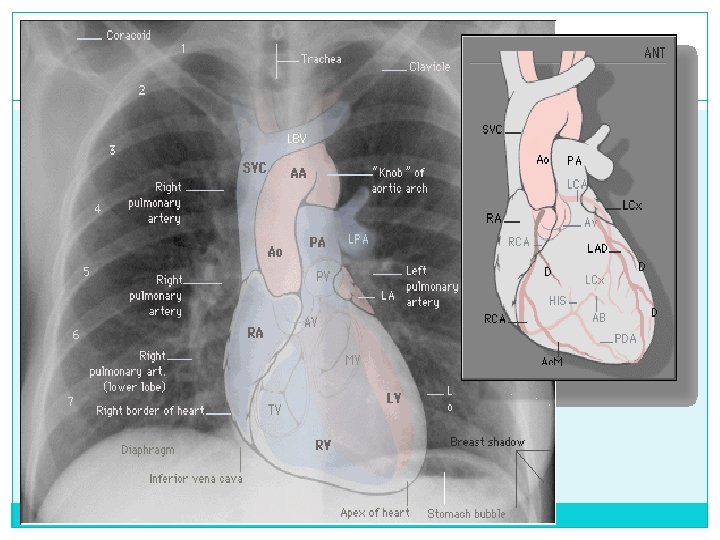

Mediastino - Posición normal: * Traquea central * Corazón 1/3 en hemitorax derecho * Arco aórtico siempre a la izquierda

Estructuras del mediastino

Corazón Indice cardiotoracico no mayor a 0. 57 (0. 53 a 0. 57) Luego del año es de 0. 50

1) Indice cardiotorácico CT index = (MRD + MLD) ID § 0 -3 sem: 0. 55 § 4 -7 sem: 0. 58 § 1 año: 0. 53 § 1 -2 años: 0. 49 § 2 -6 años: 0. 45 § > 7 años: < 0. 5

Hilio y vasos pulmonares - Bronquios - Vasos - Ganglios linfáticos - Tejido conectivo

Hilio pulmonar Difícil identificar estructuras especificas. Reducido debido al pequeño calibre de los vasos En parte a la relativa ausencia de los tejidos blandos que se interponen.